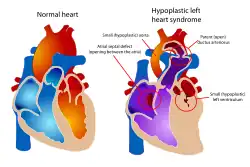

Diagram of a healthy heart and one with Hypoplastic left heart syndrome. In the heart on the right, note the near absence of the left ventricle, which normally provides systemic circulation. Following the three-stage palliation (Norwood, Glenn or hemi-Fontan, then Fontan), blood flow from the right ventricle is rerouted to serve this function, which means that an alternative source of pulmonary circulation must be provided. | |

The Norwood procedure is the first of three palliative surgeries for patients with hypoplastic left heart syndrome (HLHS) and other complex heart defects with single ventricle physiology intended to create a new functional single ventricle system.[1] The first successful Norwood procedure involving the use of a cardiopulmonary bypass was reported by Dr. William Imon Norwood, Jr. and colleagues in 1981.[2][3]

Variations of the Norwood procedure, or Stage 1 palliation, have been proposed and adopted over the last 30 years; however, its basic components have remained unchanged. The purpose of the procedure is to utilize the right ventricle as the main chamber pumping blood to the body and lungs. A connection between left and right atria (collecting chambers of the heart) is established via atrial septectomy, allowing blood arriving from the lungs to travel to the right ventricle. Next a connection between the right ventricle and aorta is created using a tissue graft from the main pulmonary artery.[4] Lastly, an aortopulmonary shunt is created to provide blood flow to the lungs from the systemic circulation. The most common shunts are the Modified Blalock Taussig shunt (MBTS) or right ventricle- to pulmonary artery shunt (RVPA or Sano shunt).

Without surgical repair, infants born with a single ventricle cardiac defect face almost certain mortality in the first year of life.[8][9][10] In these conditions, the most urgent problem is that the heart is unable to pump blood to the systemic circulation (i.e. to the body). The goal of these three surgeries is to ultimately connect the single ventricle to the systemic circulation. To accomplish this, blood flow to the lungs is disrupted, and therefore an alternative path must be created to provide blood flow to the lungs.[11]